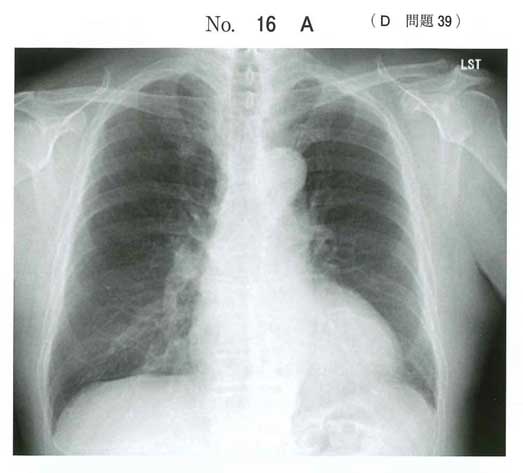

正解: a

大動脈弁+上行大動脈基部を同時に置換が必要

→ Bentall手術が適応

b 僧帽弁置換:病変なし

c 大動脈弁置換単独:大動脈拡張が残る

d 上行大動脈置換単独:ARが残る

e TAVI:AR・大動脈基部拡張では不適

ARと大動脈基部の拡張という明らかな誘導ありBentallしかないだろう。